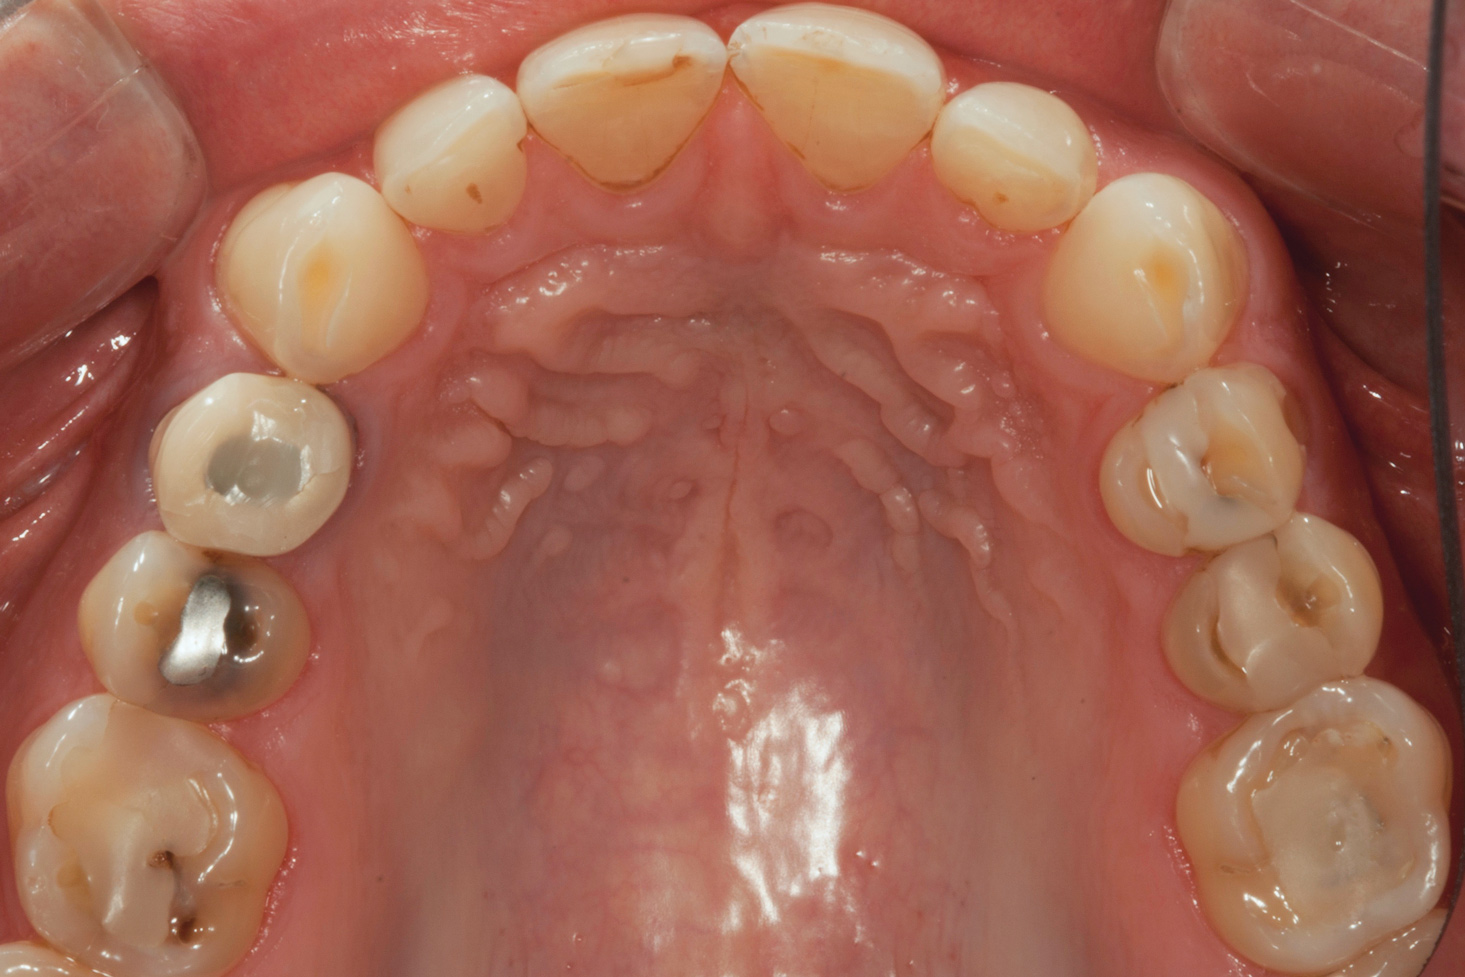

(3.) Preoperative occlusal view of lower arch with orthotic in place.

Figure 3

The patient's removable dental orthotic covered the lower bicuspids and first molars. With the orthotic in place, there was shim stock contact on all posterior teeth and on the second molars that were not covered by the appliance. However, there was no incisal overlap and a lack of anterior guidance.11 When the orthotic was removed, solid shim stock contacts were present on the second molars and the right lateral incisor. These contacts were reproduced every time the appliance was removed. The same contacts were found on the patient's mounted models, which confirmed that the joints were in centric relation. Whether the lower second molars had overerupted as a result of wearing the appliance or had already been in this position before the orthotic was fitted could not be established. Apart from these three contacts, no other teeth touched, and there was a 2-mm space between the posterior teeth, making mastication difficult. Interestingly, wear facets were present on the palatal surfaces of the upper central and lateral incisors, indicating that at some point in time, there had been significant overlap of the anterior teeth and a possible constriction of the chewing envelope. Analysis of a cephalometric radiograph showed a class II growth tendency with a reduced mandibular plane angle, which supported the theory that the patient had at one time possessed a class II occlusion.